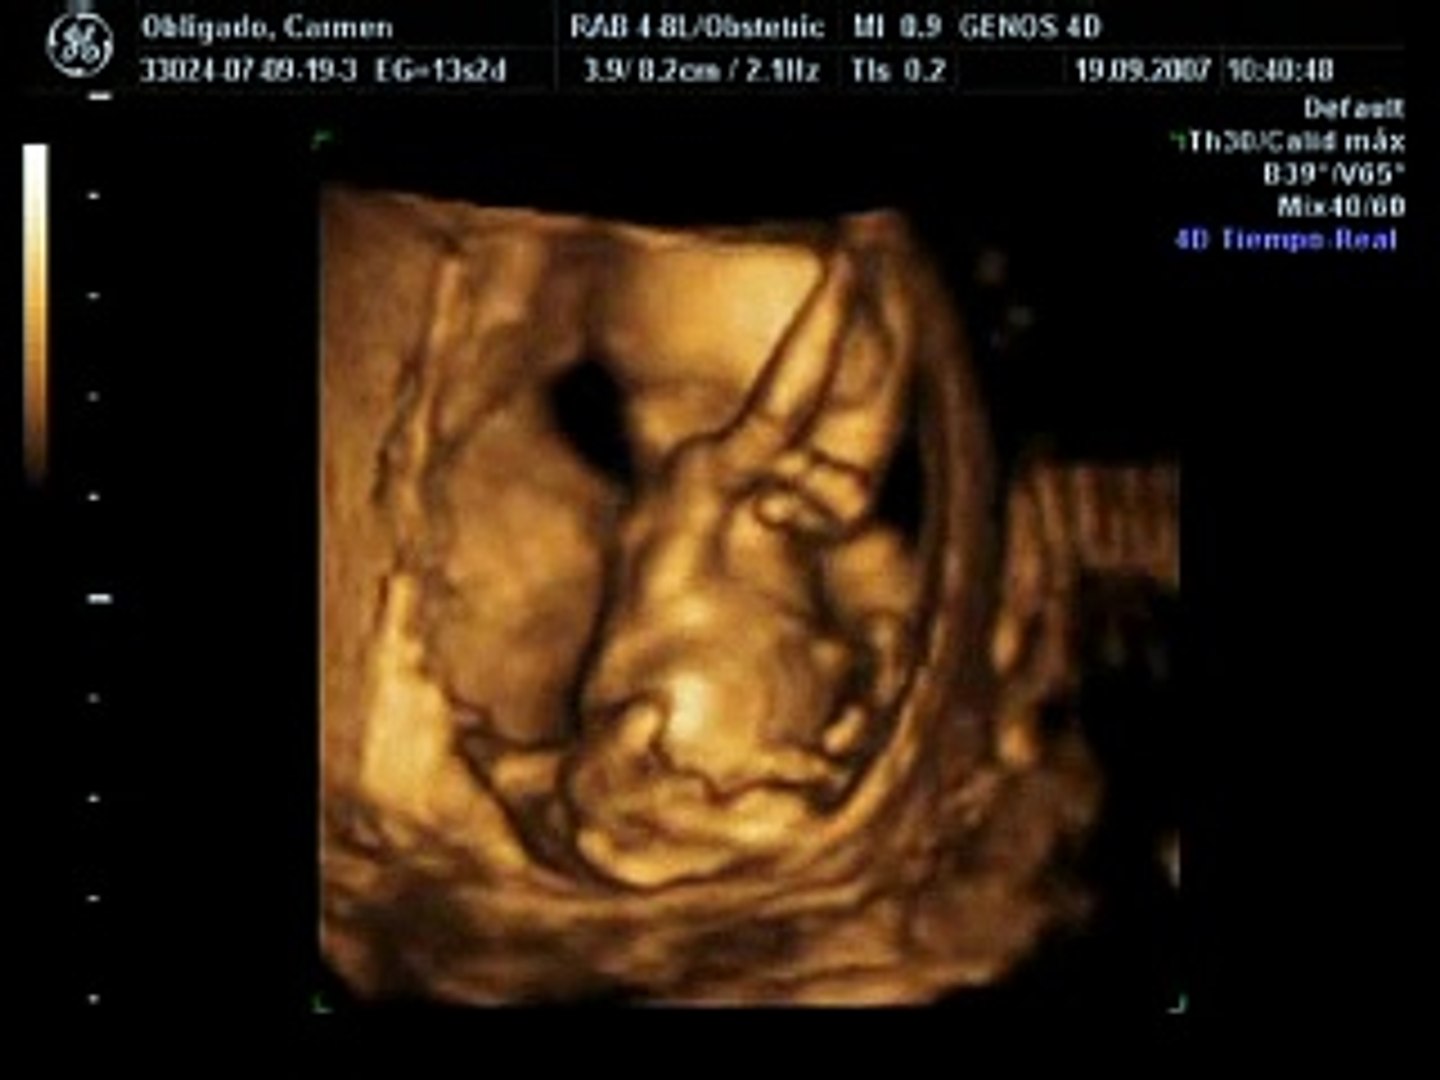

يمكن أن يبلغ طول الجنين في الأسبوع الثالث عشر من الحمل حوال 9 5 سنتيمترا ويصل وزنه إلى ما يقارب 35 جراما كما أن حجم الطفل قد يساوي حجم حبة الخوه ويصبح رأسه أكثر توزنا ويشكل حوالي ثلث حجم. اكتشفي مع بامبرز معلومات عن الجنين في الاسبوع الثالث عشر حيث تبدأ أعضائه الأساسية في العمل. شكل الجنين في الاسبوع الثالث عشر بالسونار الأسبوع الثالث عشر من الحمل أي شهر. في الاسبوع الثالث عشر من الحمل يكون طفلك بحجم ثمرة الخوخ.

سونار الحمل الاسبوع الثالث عشر Video Dailymotion